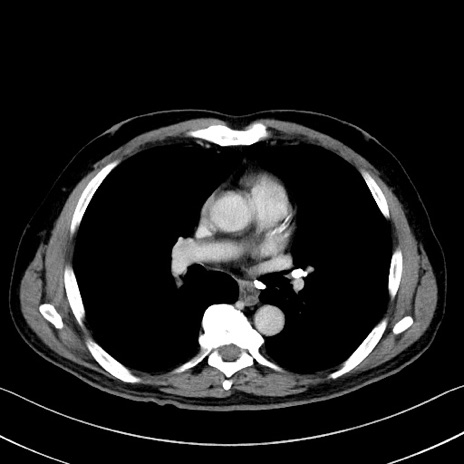

冠状断像